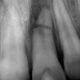

Veya tam gömük olarak kemik içinde problem yaratmadan varlığını devam ettirebilir. Çevre diş ve dokulara zarar vermeyen yani çekilmesi gerekmeyen 20 yaş dişlerinin endodontik tedavi açıdan diğer dişlerden hiç bir farkı yoktur. Ağız içindeki her dişe olduğu gibi bu dişlere de endodontik tedavi uygulanabilir.

İleri yaşlarda protez gereksinimi düşünüldüğünde 20 yaş dişlerinin son derece kritik rol oynayacağı gerçeği de gözden kaçırılmamalıdır. Dolayısıyla bu dişler çekilmeleri gerekmedikçe ağızda tutulmalı ve her türlü koruyucu tedavi uygulanmalıdır.